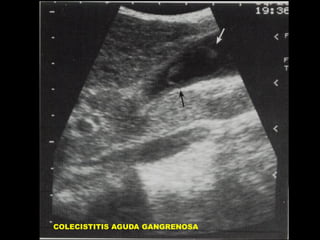

Colecistitis Gangrenosa

SEPTOS DENTRO DE LA

VESICULA BILIAR

• MEMBRANAS INTRALUMINALES

EN LA COLECISTITIS AGUDA

GANGRENOSA.

COLECISTITIS AGUDA GANGRENOSA